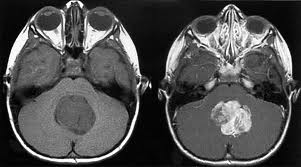

Dandy Walker Syndrome merupakan suatu sindrom (kumpulan gejala) yang terjadi pada seorang anak akibat tidak terbentuknya “pintu keluar” cairan otak dari dalam kepala. Dalam bahasa medis, pintu keluar ini disebut dengan suatu lubang khusus yaitu yang dinamakan dengan “Foramen Luschka dan Magendie”. Dalam teorinya, cairan otak manusia tersebut berada di dalam rongga cairan otak yang setiap hari diproduksi di dalam kepala dan setiap hari juga dibuang ke tubuh kita. Pada kondisi tertentu terjadi gangguan aliran cairan otak tersebut sehingga terjadilah penumpukan cairan otak yang disebut dengan “Hidrosefalus”. Hal ini akan berdampak terjadinya pembesaran rongga cairan otak yang akan menekan jaringan otak di sekitarnya. Pada Dandy Walker Syndrome, tidak terbentuknya pintu keluar ini yang mengakibatkan gangguan aliran cairan otak, pembesaran pada rongga cairan otak di sekitar otak kecil (ventrikel IV), disertai pula dengan terbentuknya kista besar di daerah otak kecil (serebelum), sehingga sebagian otak kecil (bagian tengah dari otak kecil) kemudian tidak tumbuh. Tidak tumbuhnya ini kemungkinan karena terhambat oleh kista berisi cairan otak yang menumpuk tersebut.

Secara logis, selain adanya kerusakan akibat hidrosefalus, pada Dandy Walker Syndrome juga terdapat gangguan pada pembentukan otak kecil (serebelum). Otak kecil yang berfungsi sebagai pusat pengatur keseimbangan tubuh, pusat pengatur koordinasi tubuh dan pusat pengatur tonus otot di seluruh tubuh, akan terganggu fungsinya pada Dandy Walker Syndrome. Si anak penderita Dandy Walker Syndrome diprediksi akan sulit menjaga postur tubuh tegak maupun berjalan, kesulitan dalam mengkoordinasikan gerakan tangan dan kaki serta terdapat kelemahan pada sistem alat geraknya akibat tonus otot yang tidak adekuat.

Kabar mengenai prognosis ke depan yang harus saya sampaikan pada orangtua anak penderita “Dandy Walker Syndrome” memang tidaklah sebaik pada hidrosefalus saja. Gangguan sistem organ yang begitu kompleks sering membuat sang anak tidak dapat bertahan hidup lama. Oleh karena itu, diagnosis “Dandy Walker Syndrome” ini harus ditegakkan secara jelas dan hati-hati. Upaya pertolongan harus tetap diberikan, sembari melihat dan berharap akan kekuatan misteri regenerasi otak dan organ lain pada seorang anak kecil. Kegagalan pembentukan otak kecil (serebelum) saja, belum tentu masuk katagori “Dandy Walker Syndrome”. Seluruh gejala-gejala lain harus ditelusuri dengan benar, untuk mendiagnosis dengan tepat penyakit ini.